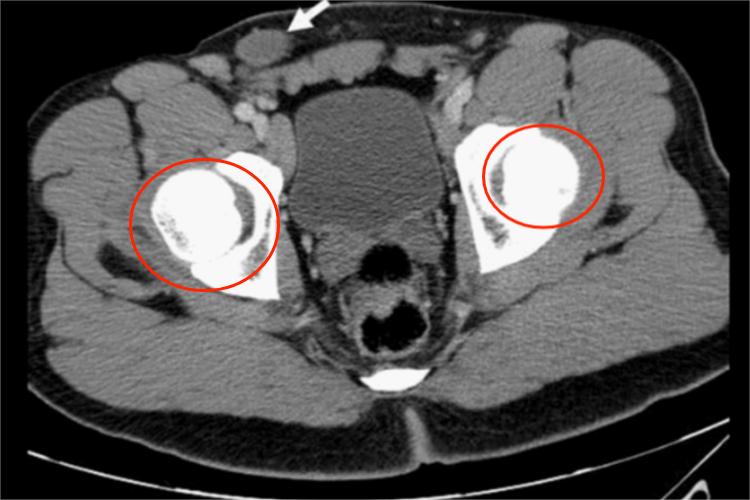

通过腹腔镜检查可以查看到腹腔内存在有隐睾,隐睾CT则表现为圆形软组织肿块,边界清楚,轮廓光整,密度均匀。